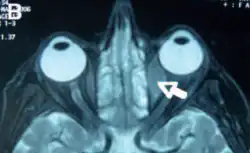

Orbital lymphoma

Orbital lymphoma is a common type of non-Hodgkin lymphoma that occurs near or on the eye. Common symptoms include decreased vision and uveitis. Orbital lymphoma can be diagnosed via a biopsy of the eye and is usually treated with radiotherapy or in combination with chemotherapy.